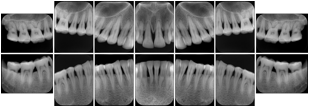

Table OO.1.1-1 shows structured display standard templates, where Viewset ID is based on the Japanese Society for Oral and Maxillofacial Radiology (JSOMR) classification provided by JIRA (Japan Medical Imaging and Radiological Systems Industries Association, www.jira-net.or.jp). Expected or typical teeth to be imaged location, region and designation codes are based on ISO 3950-2010, Dentistry - Designation system for teeth and areas of the oral cavity. For all the hanging protocols listed in OO.1.1-1, the value to use for Hanging Protocol Creator (0072,0008) is "JSOMR" and the value to use for Hanging Protocol Name (0072,0002) does not include "JSOMR" (e.g., "DL-S001A", not "JSOMR DL-S001A").